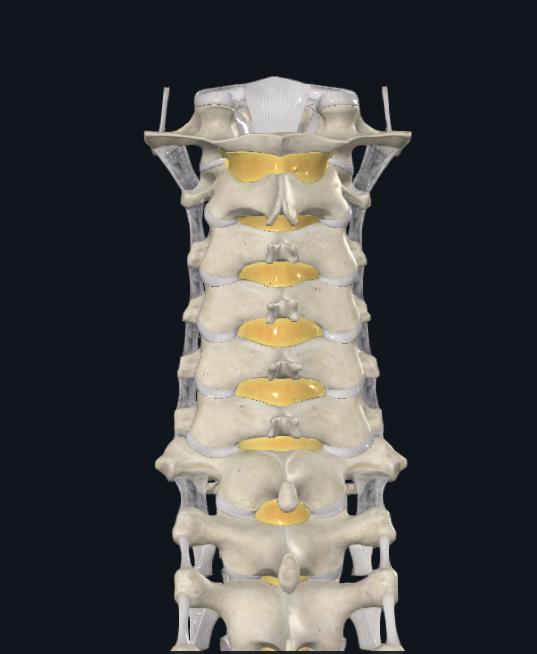

Entrypointsvarybasedonlocation

Lumbar: Confluenceofanyof:Parsinterarticularis,Mamillaryprocess,Lateralborderofsuperiorarticularfacet,Mid TransverseProcess

Thoracic: 2mm lateral and caudal to the intersection of the mid portion of facet joint and superior edge of transverseprocess.Movesmoresuperiorlywithhigherthoraciclevels

Cervical:2-3mmBelowinferioredgeofsuperiorfacet,5-6mmmedialtolateraledgeoflateralmass